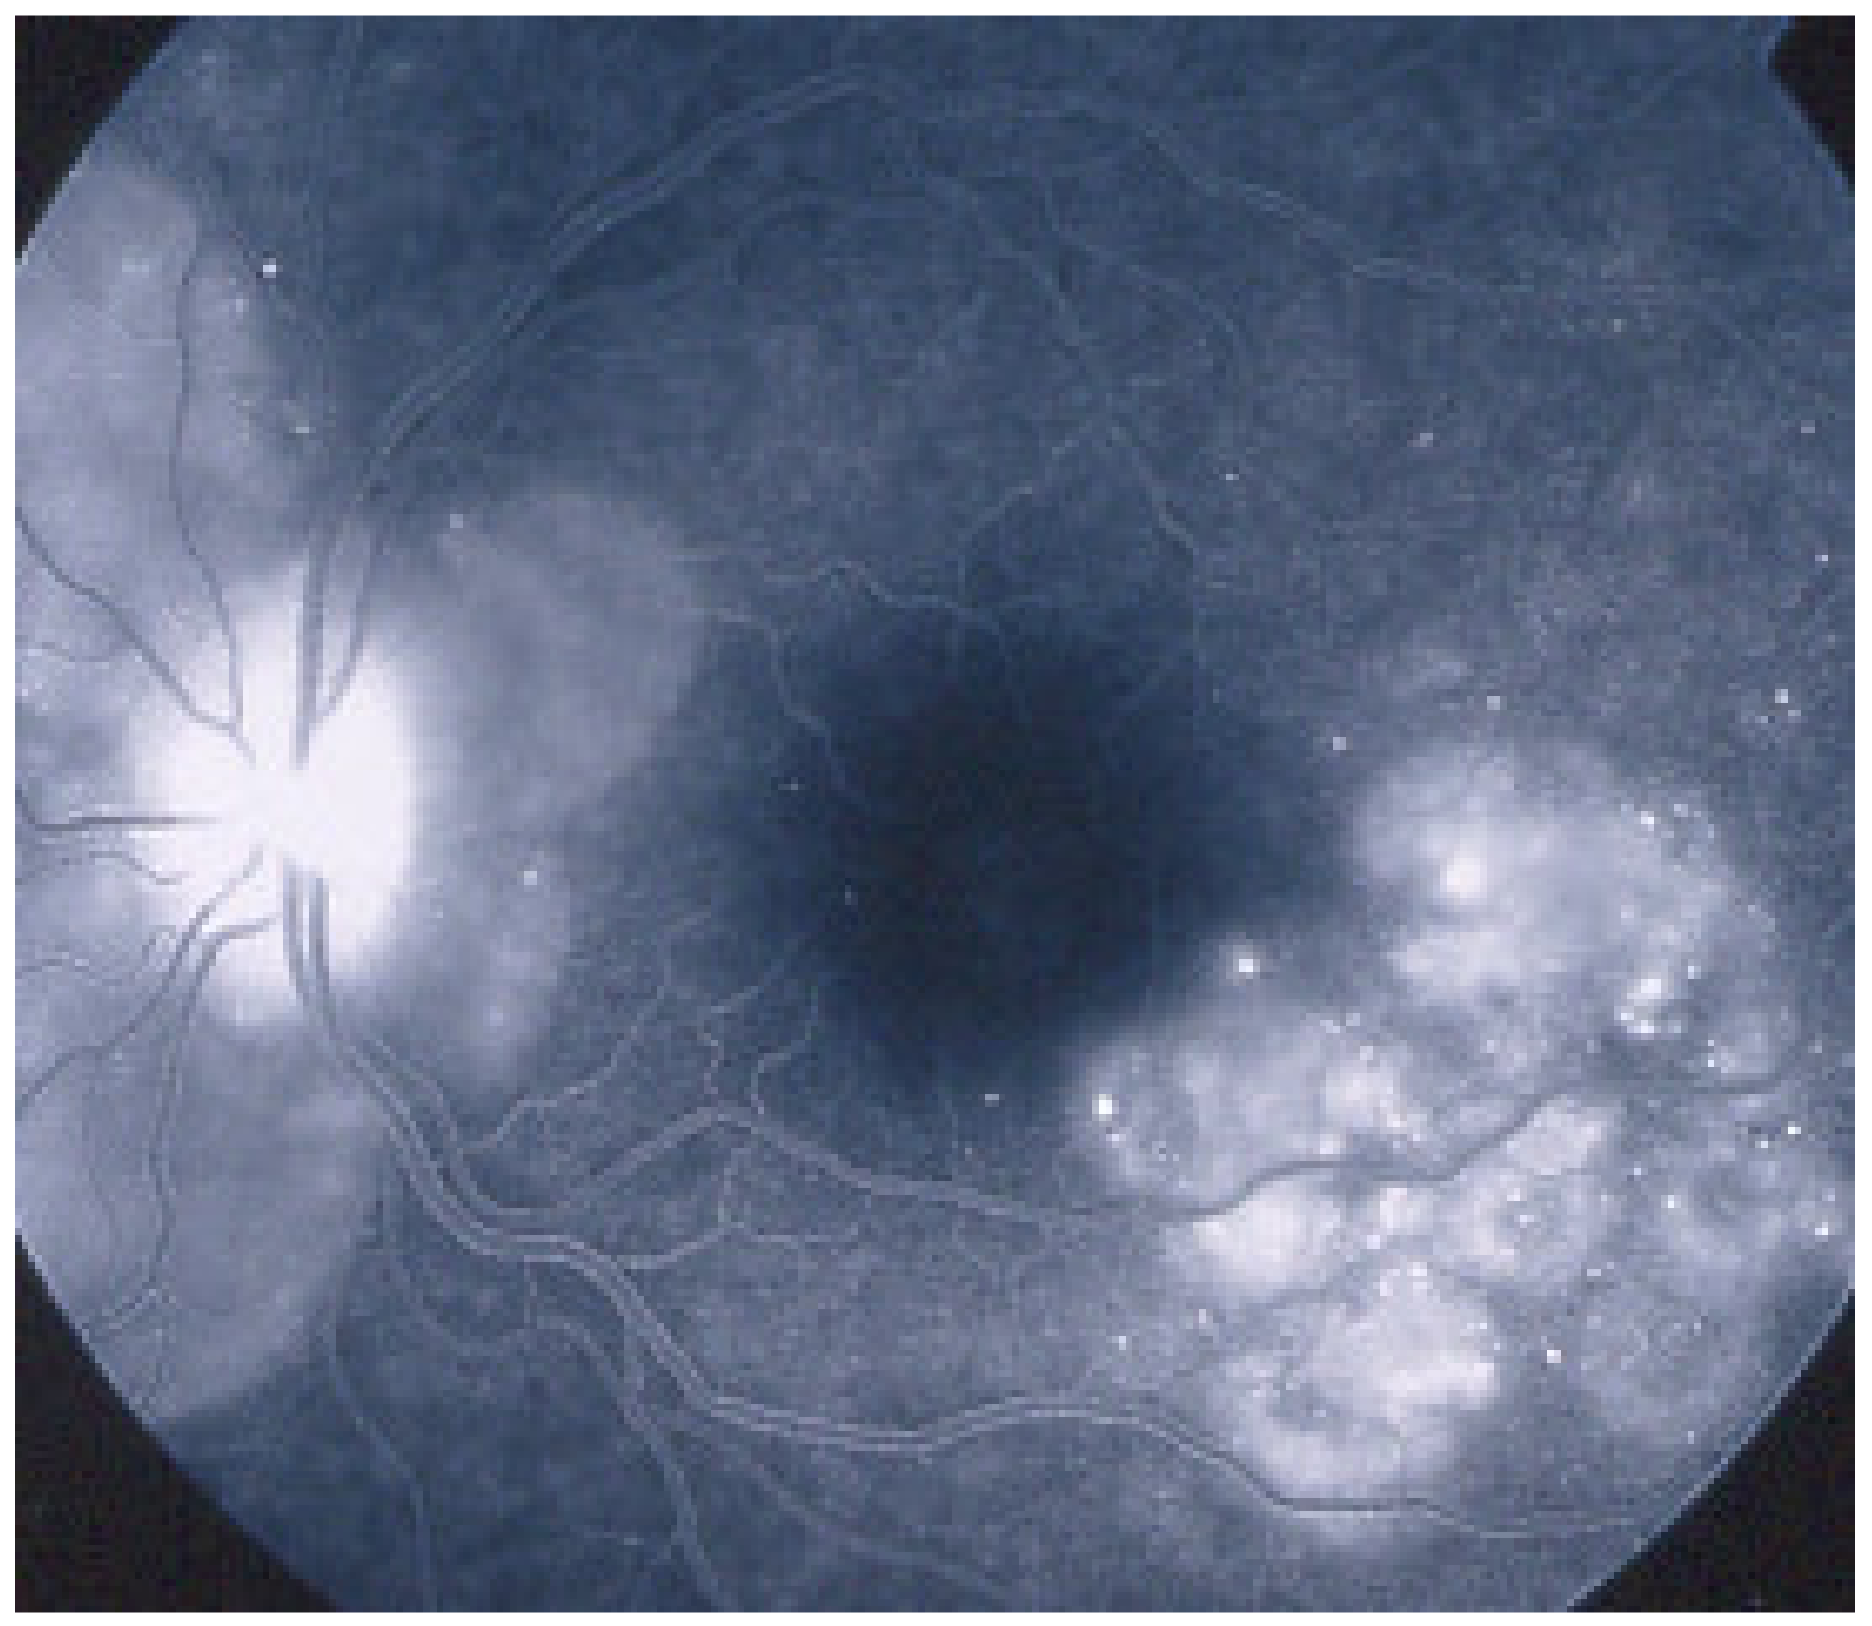

On fundus examination, the typical lesions are small randomly distributed choroidal mostly atrophic yellow-white foci with pigment spots (Figure 13) that sometimes can become adjacent to each other and form a ribbon of pearls. These lesions involve the posterior pole, around the disc, as well as the mid-periphery. In the active phases of disease, new lesions are not always visible and can be very discreet on FA, whereas ICGA is the most sensitive method to detect new lesions, as is the case in MEWDS [30,37,53,54,55]. (Figure 14) One particular feature of multifocal choroiditis is the high proportion of choroidal neovascular membranes complicating the disease, occurring in as much as one-third of cases.

As for all PICCPs, multimodal imaging is best accounting for MFC features (Table 4). On ICGA, the first set of signs identifies old scarred chorioretinal lesions and consists of hypofluorescent areas persisting up to the late angiographic phase, distributed at random in the fundus, corresponding to late hyperfluorescence on FA, typical for chorioretinal atrophy from scars of previous inflammatory episodes seen on colour fundus photos. The second set of signs can be seen in addition to the previously described signs when choroiditis recurs or can be seen in the absence of scars when it is the first episode. The signs consist of hypofluorescent areas, either silent on fluorescein angiography or hyperfluorescent in the late phase and usually not visible on fundus examination, representing areas of new inflammatory involvement (Figure 14). As in many PICCPs, some cases may present peripapillary hypofluorescence, translating functionally into an enlarged blind spot [18,36,54,55] (Figure 15). The hypofluorescent areas can completely regress if inflammation suppressive treatment is started promptly. In a substantial proportion of cases, the extent of ICGA hypofluorescence reflecting choriocapillaris hypoperfusion or nonperfusion is far more widespread than visible lesions let suspect, showing widespread areas of late occult hypofluorescence with absolutely no signs visible on fundus examination or on fluorescein angiography (Figure 15).